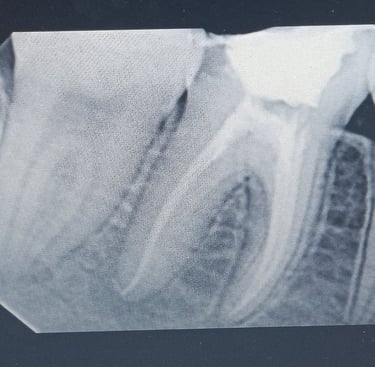

Root Canal Treatment (RCT)

A painless procedure to remove infection from inside the tooth, preserving your natural teeth and preventing further decay.